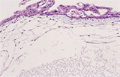

• 胞状奇胎(全、部分)ミクロ像(HE弱拡大):

• 胞状奇胎(全、部分)ミクロ像(HE中拡大)